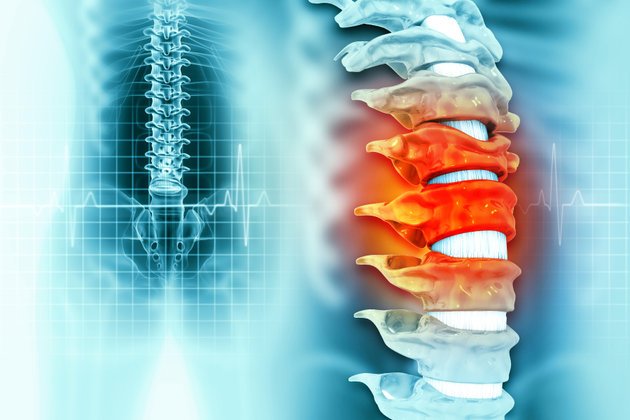

Parapleji, diğer adıyla omurilik felci, her iki bacakta ve genel olarak karın ile bel bölgesini kapsayan alt ekstremitelerde hareket ve his kaybı ile tanımlanan bir hastalıktır. Omurilik felcinin benzeri olan paraparezi ise her iki bacağın kısmi felcidir. Yani paraplejide ayaklarda hareket olmasına rağmen, güç kaybı sebebiyle hasta yardımsız yürüyemez.

Düşme, kurşun yarası, araba veya motosiklet kazası gibi durumlar sonucu oluşan omurilik hasarı paraplejiyi tetikleyebilir. Ayrıca omurga tümörleri de sebepler arasında yer alabilir. Omuriliği çevreleyen kemik yapısının anormal bir şekilde yana kayması olarak tanımlanan skolyoz, ilerlemesi durumunda omurilik felcine yol açabilir. Doğumsal bir rahatsızlık olan spina bifida, omurga kemiklerinin kapanmaması ile sonuçlanarak omurilik felcinin bir diğer nedeni olabilir.

Hasar gören omurilik bölgesinin aşağısında refleks, his ve hareket kaybı söz konusu olabilir. Zedelenen bölgenin yeri ve omuriliğin hasar derecesine bağlı olarak hastalarda mesane ve bağırsak kontrol kaybı ile cinsel işlev bozuklukları görülebilir. Omurilik tamamen hasar gördüğünde, hasarın olduğu bölgeden itibaren tüm alt ekstremitede hiçbir his ve hareket olmaması mümkündür. Kısmi omurilik hasarında ise büzücü kaslar olarak bilinen sfinkter kasların kontrolü bozulmaz.